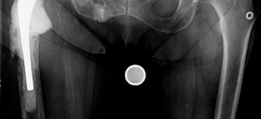

History of presenting complaint : Presents with a draining wound and well-fixed cementless components with a constrained liner due to absent abductor mechanism (Fig. 19.12). Treated with Prostalac and six weeks of IV antibiotics (Fig. 19.13). At the 6-week point, the patient sustained a ground level fall with an acetabular fracture and displacement of the acetabular Prostalac (Fig. 19.14).

Fig. 19.12 AP X-ray right THA with well-fixed components and severe osteoporosis with healed inferior pubic ramus fracture